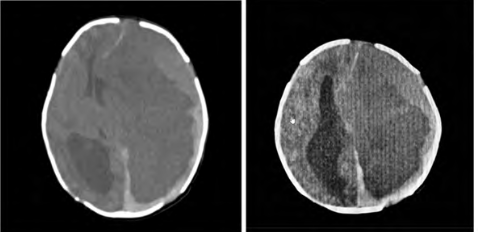

Hemophilic Neonate with Massive Subdural Hematoma Rescued Using Life-Saving Management: A Case Report

Binoy Vadakke Nellissery, Chelladurai Pandian Hariharan, P Babu Balachandar, Sai Srinivas Bhagavatula, Sandeep Kuchi and Geevarghese Nithin Panicker. 12(12): 01-04.